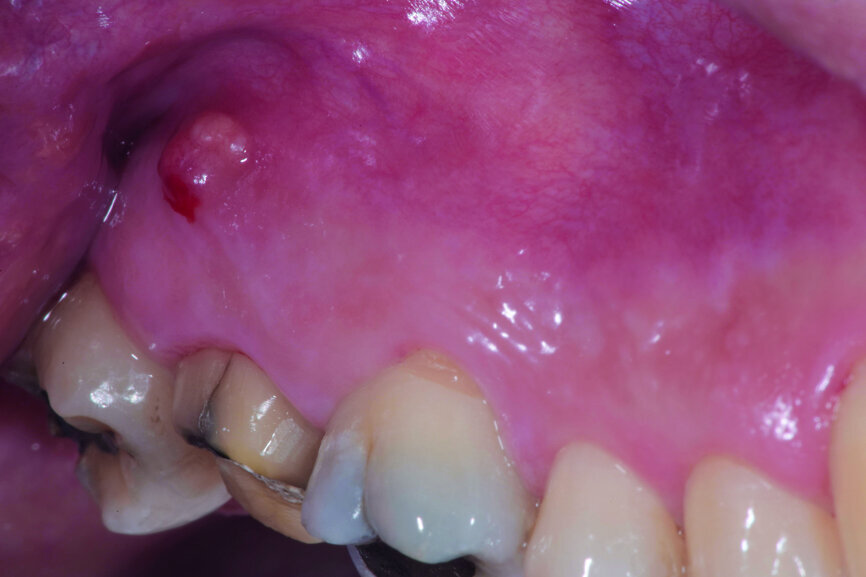

The left mandibular second molar of a 35-year-old female patient had been compromised because of a vertical root fracture and a large periapical lesion was present. After explanation and informed consent, the treatment was scheduled. The right mandibular third molar was preferred as a donor to the left mandibular third molar because of a more compatible anatomy and for an easier stabilisation. After local anaesthesia of both the donor and the recipient sites with 2 per cent mepivacaine with 1:100,000 adrenaline, the left mandibular second molar was extracted and the alveolus debrided. Then the donor tooth was atraumatically extracted, quickly repositioned in the recipient site and stabilised with sutures at about 1.5–2.0 mm of infraocclusion. An antibiotic (amoxicillin/clavulanic acid, 1 g, by mouth twice a day for five days) and a non-steroidal anti-inflammatory drug (ibuprofen, 600 mg, by mouth twice a day for five days) were prescribed, along with rinses with 0.2 per cent chlorhexidine. The sutures were removed after two weeks and endodontic treatment was performed after three months. The periapical lesion healed and the tooth was fully functional after 12 years (Figs. 14a–d & 15a–d).